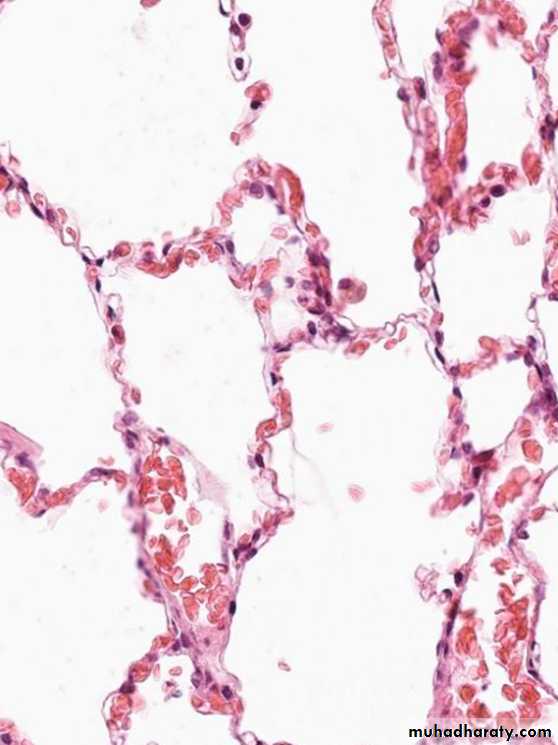

1.Acute pulmonary congestion:

Alveolar capillaries engorged with blood

variable degrees of alveolar septal edema and intraalveolar hemorrhage.